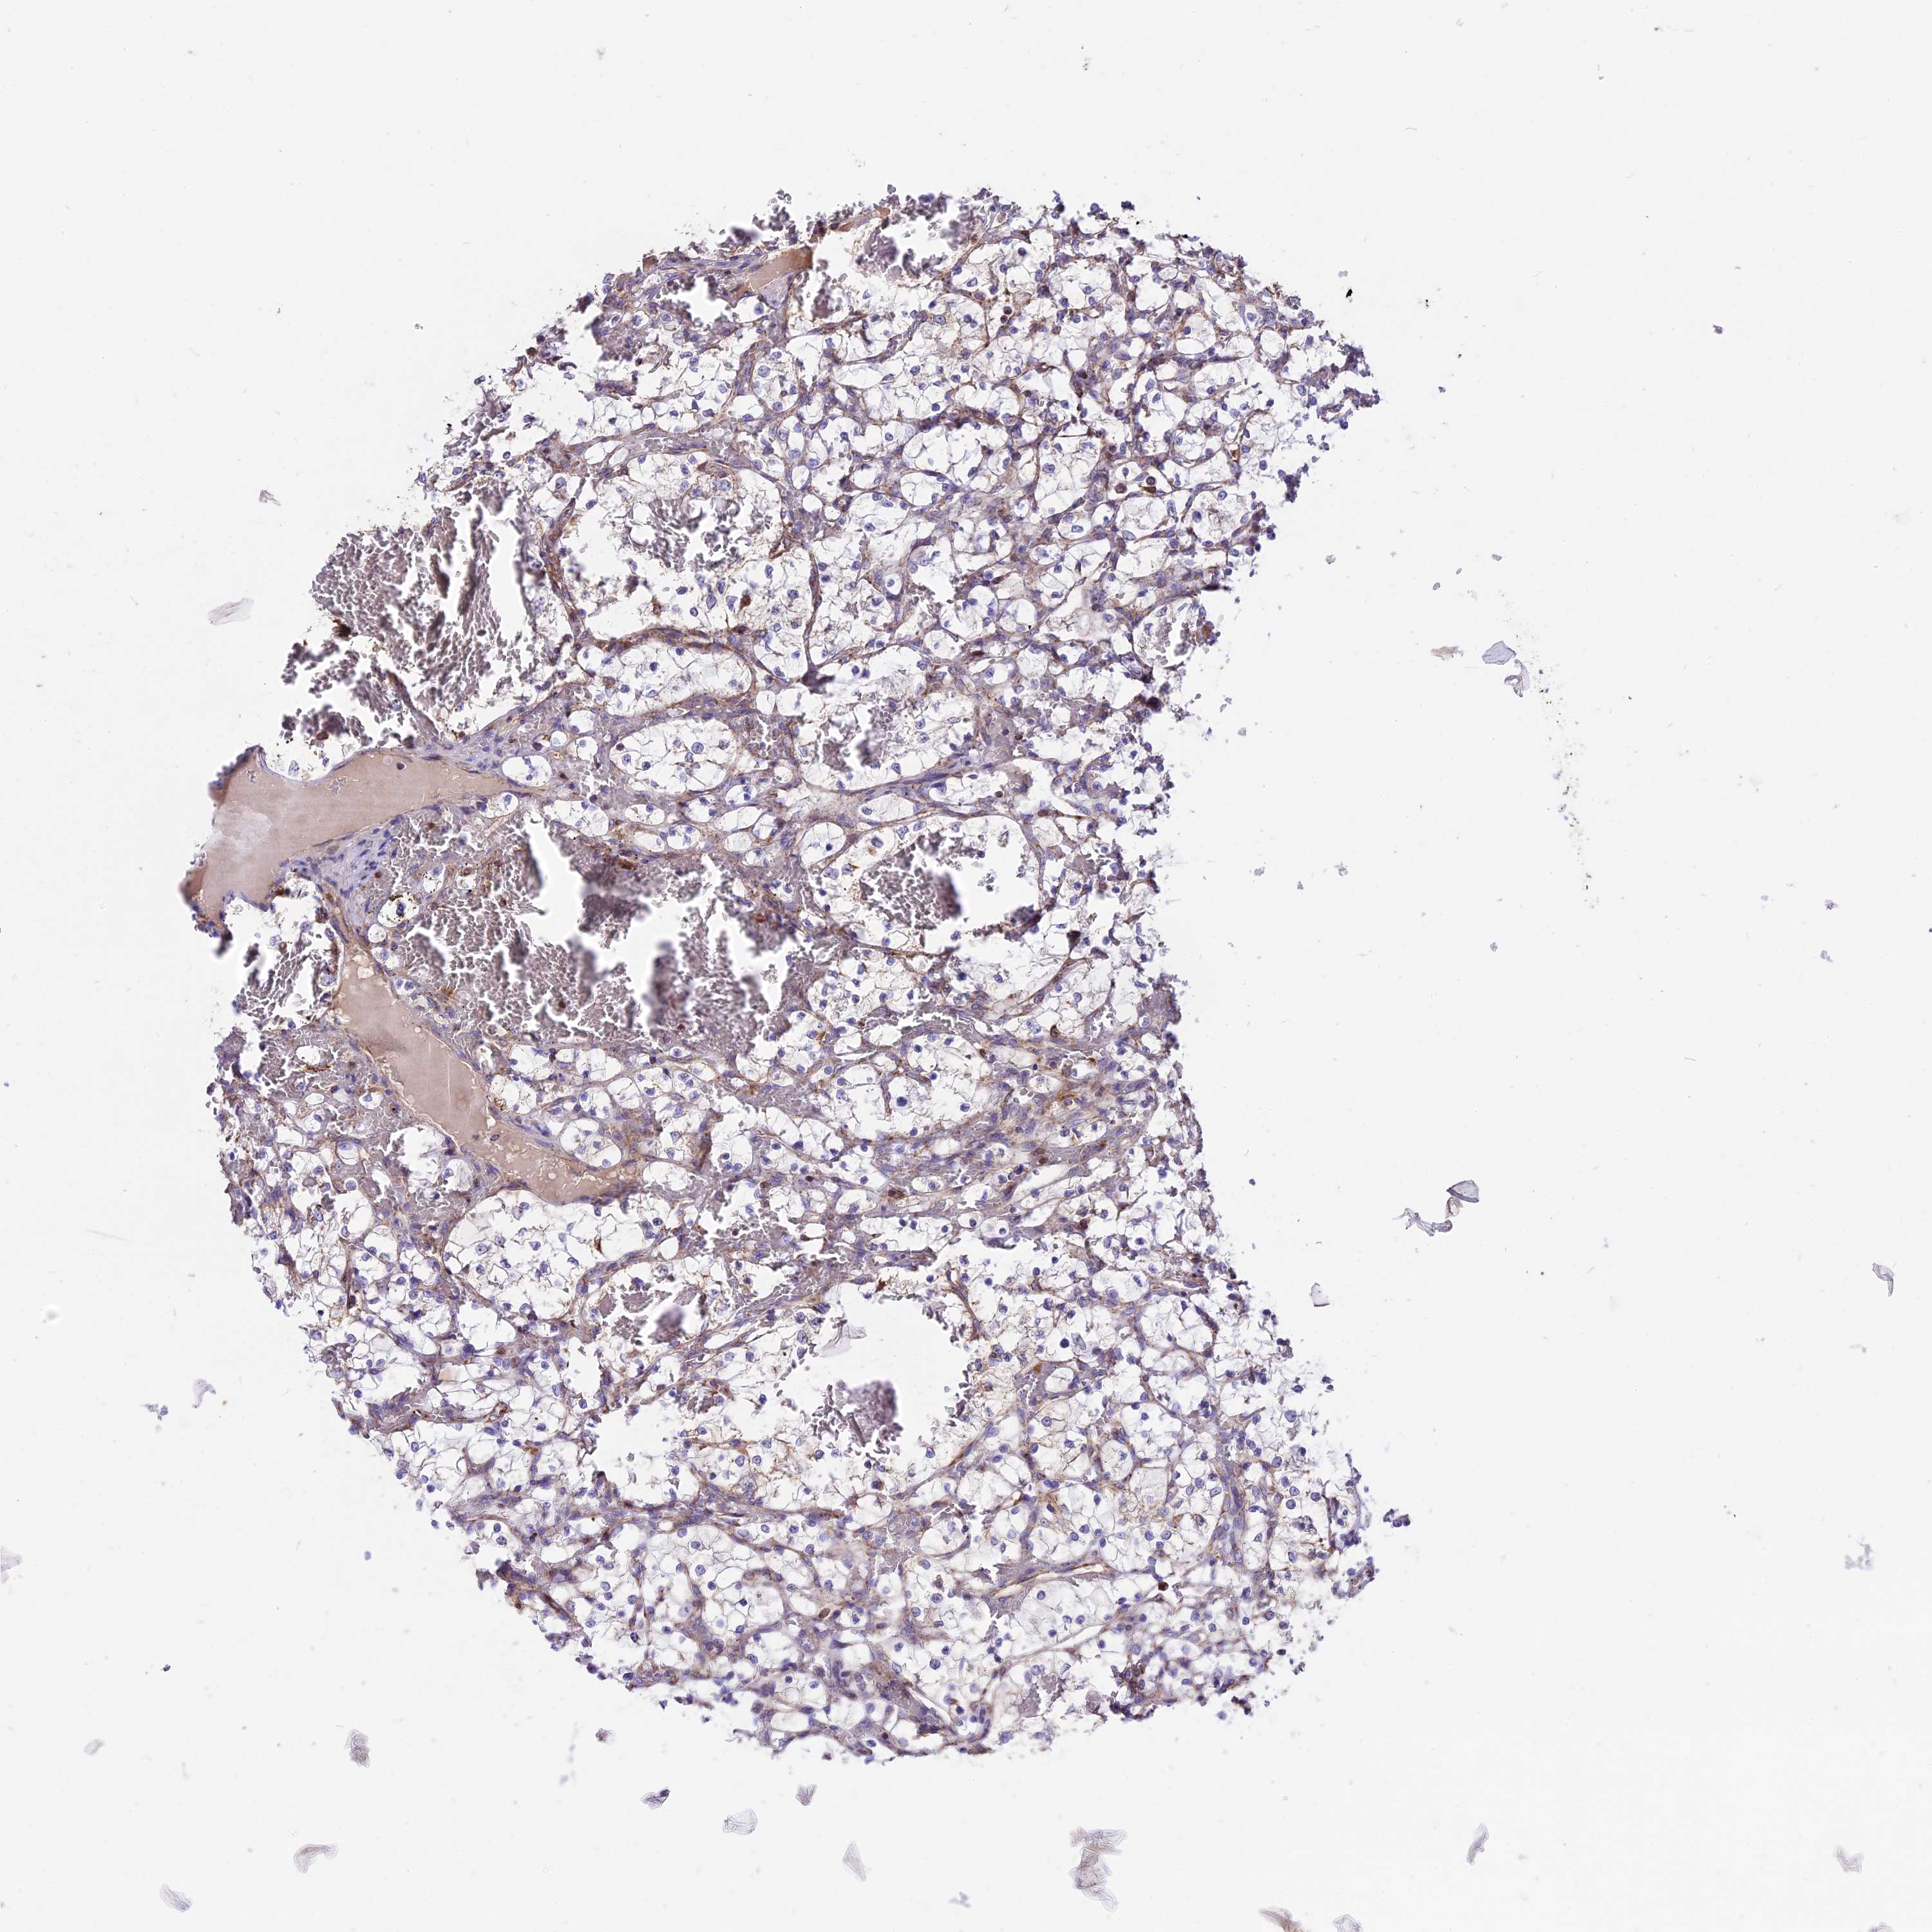

KIDNEY RENAL CLEAR CELL CARCINOMA (VALIDATION) - Interactive survival scatter ploti

The Survival Scatter plot shows the clinical status (i.e. dead or alive) for all individuals in the patient cohort, based on the same data that underlies the corresponding Kaplan-Meier plots. Patients that are alive at last time for follow-up are shown in blue and patients who have died during the study are shown in red.

The x-axis shows the expression levels (FPKM) of the investigated gene in the tumor tissue at the time of diagnosis. The y-axis shows the follow-up time after diagnosis (years). Both axes are complimented with kernel density curves demonstrating the data density over the axes. The top density plot shows the expression levels (FPKM) distribution among dead (red) and alive patients (blue). The right density plot shows the data density of the survived years of dead patients with high and low expression levels respectively, stratified using the cutoff indicated by the vertical dashed line through the Survival Scatter plot. This cutoff is automatically defined based on the FPKM cutoff that minimizes the p-score. The cutoff can be changed by dragging the vertical line or by entering a cutoff value in the square labeled "Current cut-off".

Under the Survival Scatter plot the p-score landscape (black curve; left axis) is shown together with dead median separation (red curve; right axis). Dead median separation is the difference in median mRNA expression between patients who have died with high and low expression, respectively. It is calculated as follows: median FPKM expression of dead patients with high expression - median FPKM expression of dead patients with low expression. This is intended to aid the user in visually exploring custom cutoffs and the associated p-scores and dead median separation.

Individual patient data is displayed and can be filtered by clicking on one or more of the category buttons on the top of the page. Categories describing expression level and patient information include: high, low, alive, dead, female, male and tumor stages. The scale of the x-axis can be toggled between linear and log-scale by clicking on the "x log" button. Mouse-over function shows TCGA ID, patient information and mRNA expression (FPKM) for each patient.

& Survival analysisi

Kaplan-Meier plots summarize results from analysis of correlation between mRNA expression level and patient survival. Patients were divided based on level of expression into one of the two groups "low" (under cut off) or "high" (over cut off). X-axis shows time for survival (years) and y-axis shows the probability of survival, where 1.0 corresponds to 100 percent.

COX17 is not prognostic in Kidney Renal Clear Cell Carcinoma (validation)

Best expression cut offi

Based on the FPKM value of each gene, patients were classified into two groups and association between prognosis (survival) and gene expression (FPKM) was examined. The best expression cut-off refers the FPKM value that yields maximal difference with regard to survival between the two groups at the lowest log-rank P-value. Best expression cut-off was selected based on survival analysis .

When clicking on this number, the vertical dashed line indicating cut-off, the interactive survival plot, and the Kaplan-Meier curve will be adjusted to show results based on the best expression cut-off.

: 149.67

TCGA RNA samplesi

RNA-seq data is reported as average FPKM (number Fragments Per Kilobase of exon per Million reads), generated by the The Cancer Genome Atlas (TCGA) .

Normal distribution across the dataset is visualized with box plots, shown as median and 25th and 75th percentiles. Points are displayed as outliers if they are above or below 1.5 times the interquartile range. FPKM values of the individual samples are presented next to the box plot.

Average pTPM 136.1

Number of samples 100